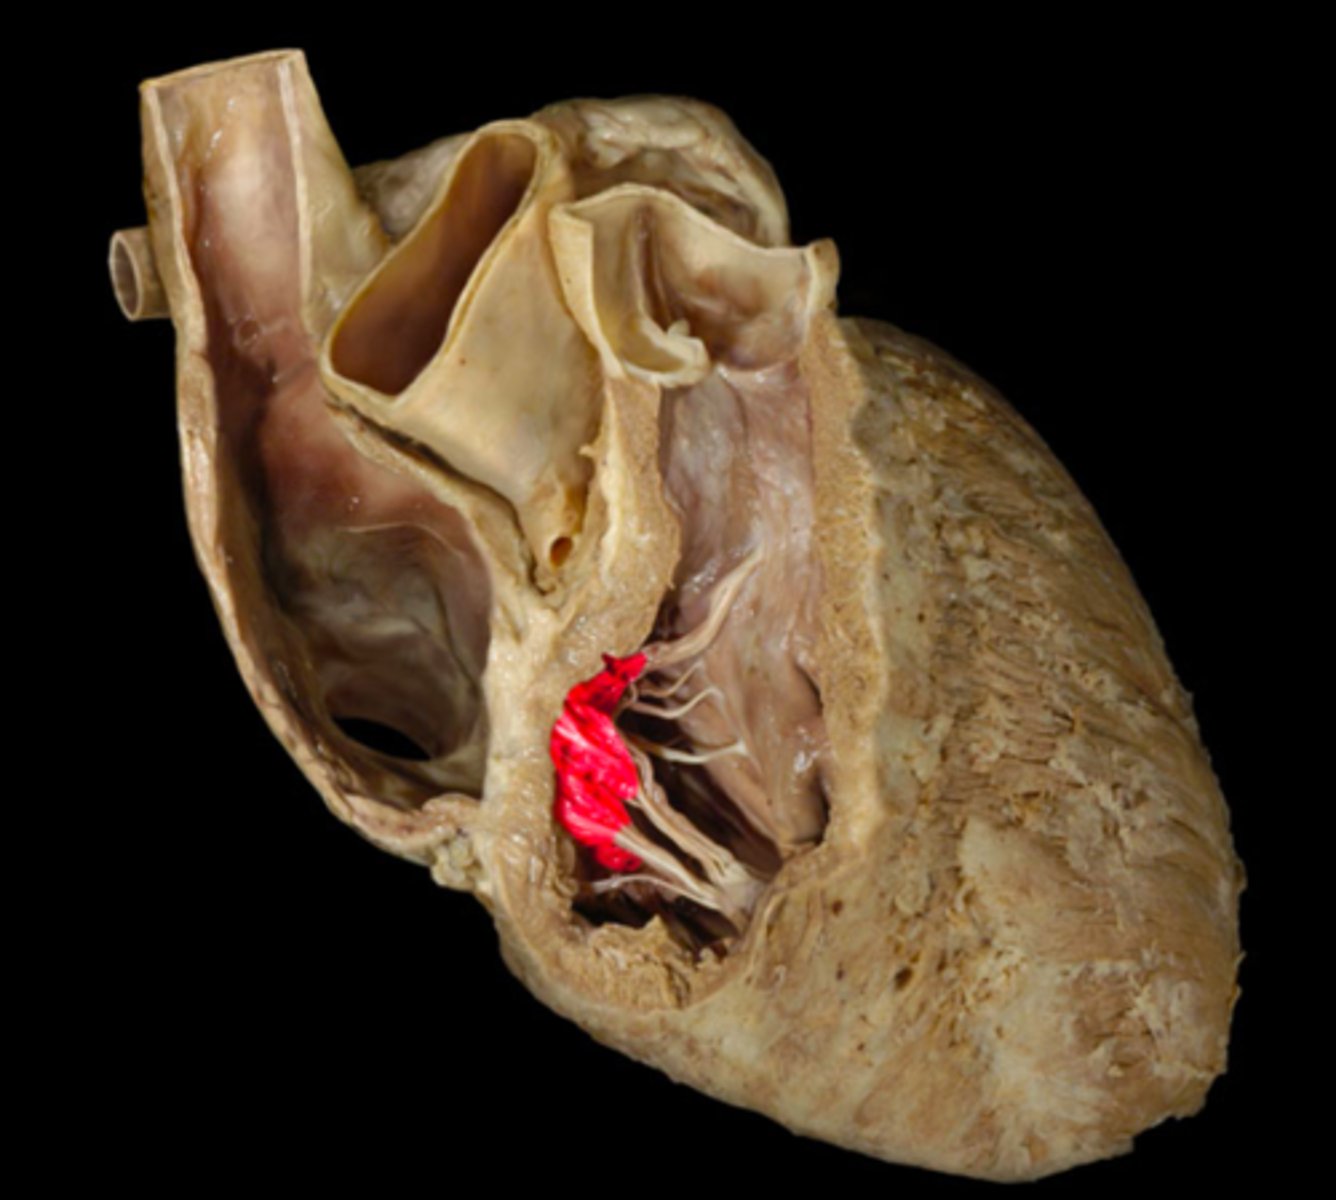

papillary muscles

cordae tendineae

trebecula carnea

moderator band (right ventricle)

muscular bundle in the right ventricle connecting the interventricular septum to the anterior papillary muscle